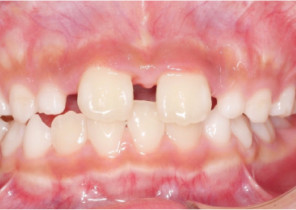

Case Report 2

7 years 11 months old, 24 stages of Invisalign® Palatal Expanders

Courtesy of Dr. David R. Boschken

Pre Invisalign Palatal Expander Expansion

Post Invisalign Palatal Expander Expansion

Post Invisalign Palatal Expander Treatment